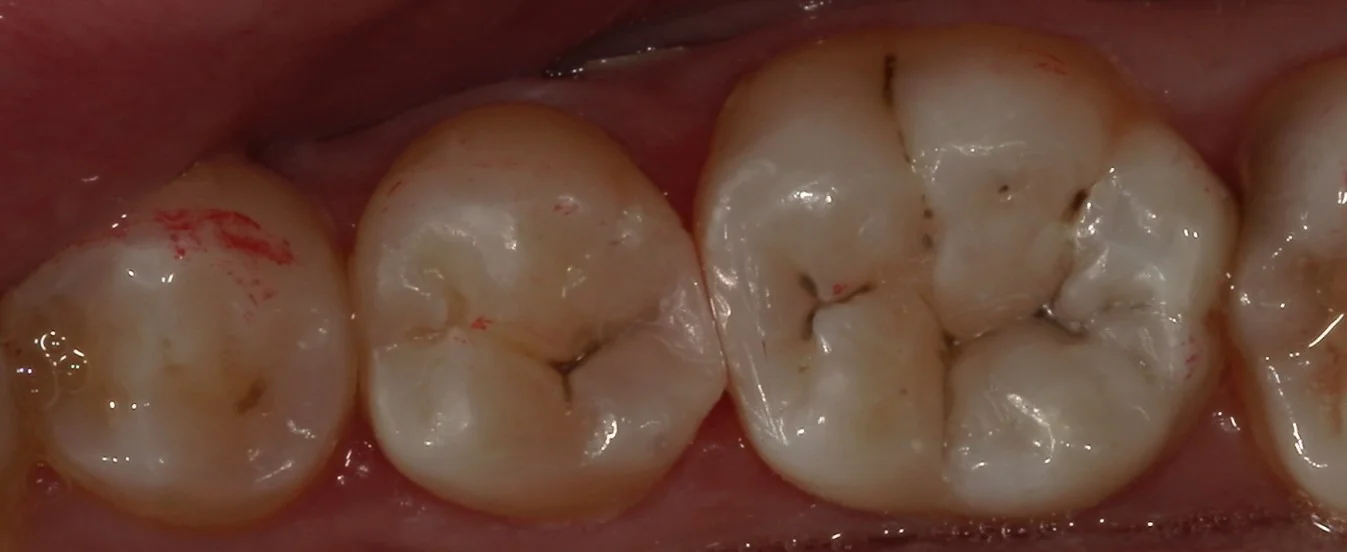

そして、詰め終わったのがこちらです。

歯の底の色を隠すように色を消せる材料を使用しながら詰めました。

歯の溝の色を本来の色に合わせて詰めましたので、違和感はなく仕上げられたかと思います。 歯との間の部分にもフロスを通しても引っ掛かりは一切ない状態に仕上げているので、問題なく使用して頂けるかと思います。 患者さんは歯科医師なので、色合わせなどの難しさも十分承知の方でしたので、非常に喜んでいただきました。